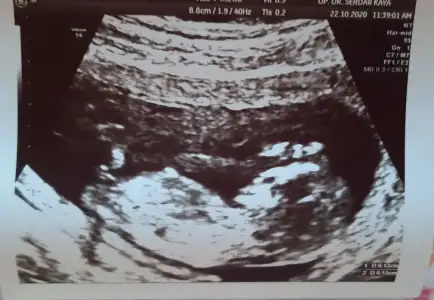

12+4..tahmininizi bekliyorum..

Eklentiler

• 20201022_181417.webp

20201022_181417.webp

32,1 KB · Görüntüleme: 91

• 20201023_150518.webp

20201023_150518.webp

34,4 KB · Görüntüleme: 80

• 20201023_150459.webp

20201023_150459.webp

40,8 KB · Görüntüleme: 79

Doktor erkek dedi ama 12.hafta olunca ben emin olamadım. Pipi fotosu da vermiş, ona da bakınca çok emin olamıyorum. Belli bir aya dek benzer gittiği için genital organlar, belki yanılmıştır diyorum..kız istediğim için..umarım bir ay sonra, yanılmışım, kızmış der doktor..